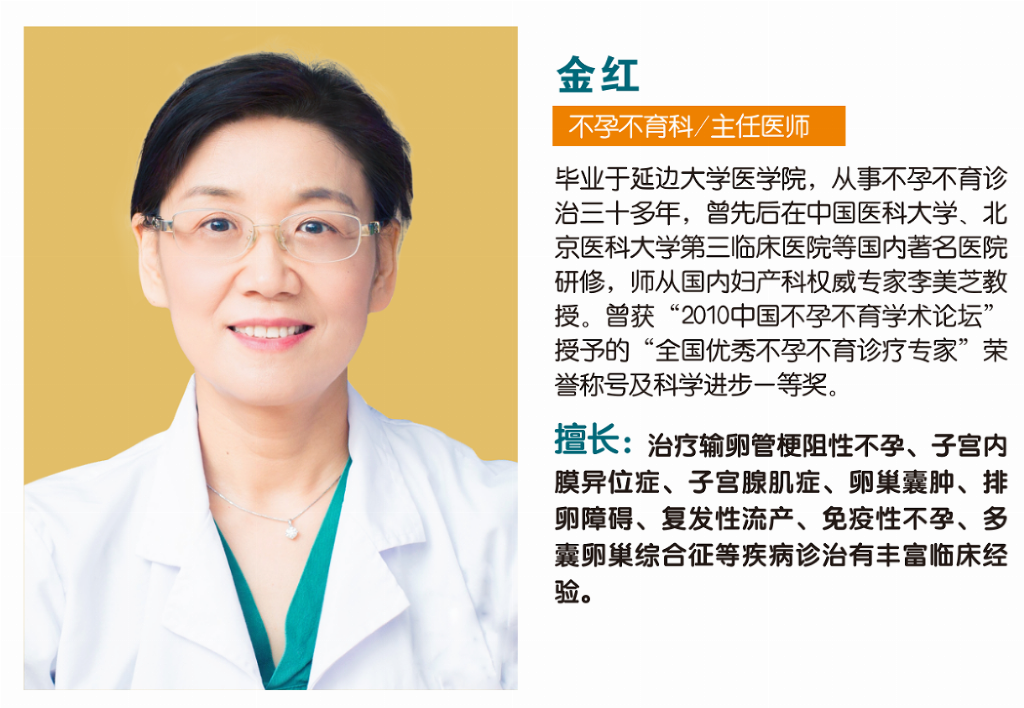

金红

基本信息

职称:主任医师

科室:广州南粤医院·不孕不育科

资历:30余年不孕不育临床经验,师从国内妇产科权威专家李美芝教授,先后在中国医科大学、北京医科大学第三临床医院等国内著名医院研修。

擅长领域(核心专长)

专攻女性不孕症,尤其擅长运用宫、腹腔镜微创技术治疗:

v 输卵管问题:输卵管梗阻性不孕、结扎复通、输卵管炎症上举

v 卵巢问题:卵巢早衰、多囊卵巢综合征、排卵障碍、卵巢囊肿

v 子宫问题:宫腔息肉、宫腔粘连、子宫内膜异位症、子宫肌瘤

v 疑难不孕:反复流产、胎停育、免疫性不孕

v 优生优育指导、高龄备孕指导、科学备孕指导